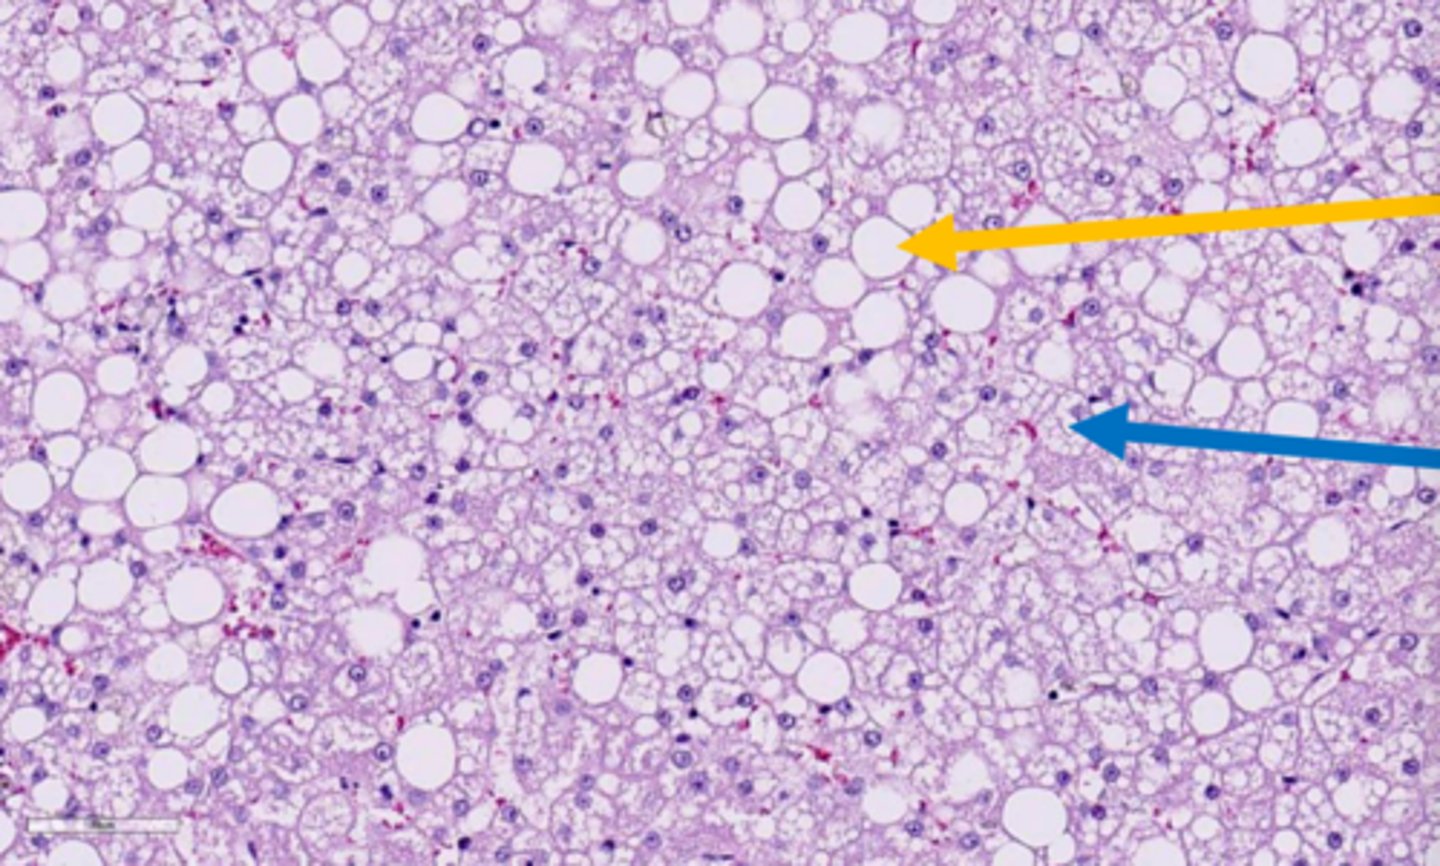

macrovesicular hepatic lipidosis

yellow arrow?

<p>yellow arrow?</p>

microvesicular hepatic lipidosis

blue arrow?

<p>blue arrow?</p>